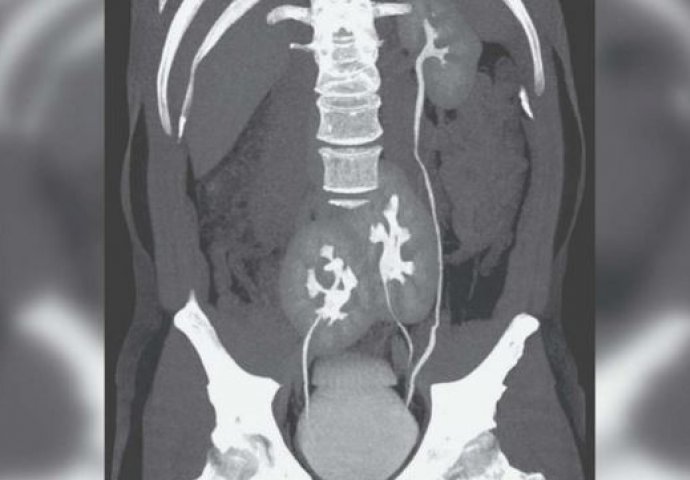

Čovek iz Brazila je prošle nedjelje posjetio bolnicu u Sao Paolu zbog bola u donjem dijelu kičme. Vjerovao je da je problem u diskus herniji i želio je da to snimi. Snimak je pokazao da je zaista u pitanju diskus hernija, ali i da čovjek ima tri bubrega sa kojima je rođen, a da to nije ni znao. Lijevi bubreg bio mu je sasvim u redu, a pokazalo se da ima i dva spojena desna bubrega.

Mokraćovodi, odnosno ureteri ovog muškarca, spojeni su na ulazu u bešiku.

– Nikad nismo vidjeli ništa slično ovome. Ostali smo bez teksta. Prvo smo se zabrinuli da mu to utiče na zdravlje, međutim, dodatno iznenađenje bilo je da mu to uopšte ne remeti bilo kakvu funkciju – kaže za medije dr Renato Foresto, jedan od ljekara iz ove bolnice koji je objavio i naučni rad o pacijentu sa ovim rijetkim stanjem.

Analize krvi pokazale su da mu bubrezi savršeno rade, a i opšte zdravstveno stanje, ako se izuzme kičma, mu je odlično. Tako je pacijent dobio lijekove protiv bolova i poslat je kući.

Ovo stanje, zvano supernumerarni bubreg, je ekstremno rijetko, i za sada je u istoriji zabilježeno svega 100 ovakvih slučajeva.